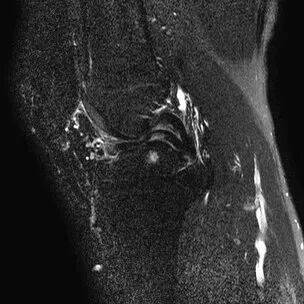

半月板撕裂定义与显示

1、半月板显示:以T2-WI加脂肪抑制为最好.2、半月板病变:最常见损伤是撕裂伤3、病因:慢性退变性撕裂和急性外伤性撕裂4、诊断方法:当半月板内出现线样高信号到达其游离缘或关节面时,即可诊断半月板撕裂5、病变信号变化:T1WI为线样稍高信号,T2(FS)或T2*WI信号更高6、半月板球形及线行高信号影未达关节面,为其慢性损伤或退行性改变(变性)7、MR诊断半月板撕裂的准确度达90-97%,特异性为94%,假阳性高于假阴性,主要是将膝横韧带与外侧半月板相邻的国肌腱鞘等误认为半月板撕裂.

最常见类型:斜行撕裂表现为:在矢状面上见III级高信号到达半月板关节面的上缘或下缘

半月板斜行撕裂